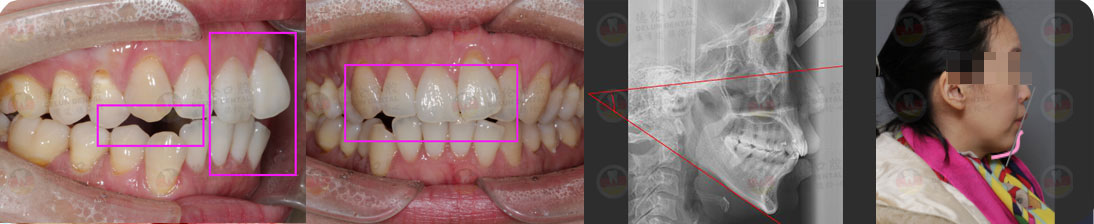

- 【診斷】

骨性Ⅱ類高角伴擁擠

上頜前突、下頜后縮、下前牙唇傾

下中線右偏2.5mm,21 35°扭轉(zhuǎn)13低位

打造醫(yī)生:德倫口腔正畸中心熊小琴主任

- 【治療方案】

拔除3顆多余的咬合不正的智齒,通過(guò)支抗釘控制

失狀向和垂直向,推上、下牙遠(yuǎn)移解決擁擠改善前

突,使整個(gè)頜平面逆時(shí)針旋轉(zhuǎn),改善了下頜后縮的

情況

矯治前后對(duì)比

牙列整平排齊,前牙內(nèi)收;覆蓋、覆合正常;尖牙和磨牙達(dá)到中性關(guān)系;上下中線對(duì)齊;下頜后縮改善